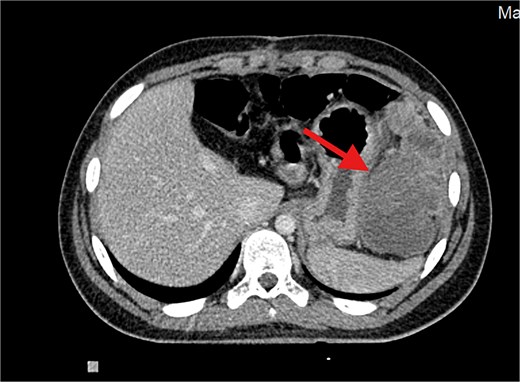

Contrast-enhanced axial CT image showing a large, heterogeneously enhancing soft tissue mass measuring ⁓11 × 5.5 × 8.3 cm in the left subphrenic region, abutting, and indenting the greater curvature of the stomach. The lesion demonstrates internal cystic and necrotic components, consistent with a recurrent undifferentiated embryonal sarcoma.